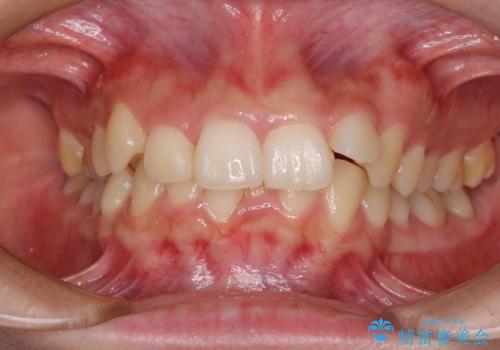

下顎前歯が隠れて突出した口元 ワイヤー装置での抜歯矯正

- 前歯のデコボコと口元の突出感を気にして来院された患者様です。

下顎骨の左右差や、上顎骨の前方位などが認められたため、上下左右の第1小臼歯4本を抜歯し、ワイヤー装置にて矯正治療を行うこととしました。